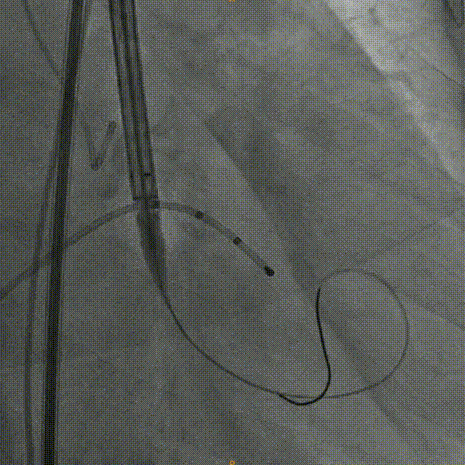

Venus26号瓣膜释放:前三分之一慢放精准定位,中三分之一快放使瓣膜快速进入工作状态。

Venus26号瓣膜释放:位置良好,轻度反流,遂完全释放后采取后扩。

后扩后瓣膜最终形态。